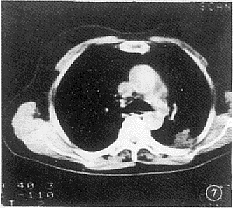

2.7 胸膜改变:球形肺炎中20例邻近胸膜呈广泛均匀性增厚(95%),但无局限性结节(图6)。21例周围型肺癌中10例胸膜凹陷征阳性(48%)。3例见胸膜不均匀增厚,其中2例有局限性小结节形成(图7)。

图6 左上叶舌段球形肺炎,病变与邻近胸膜以广基相连,胸膜广泛均匀性增厚

图7 左下叶背段周围型肺癌,邻近胸膜受累呈不规则增厚,有局限性小结节形成